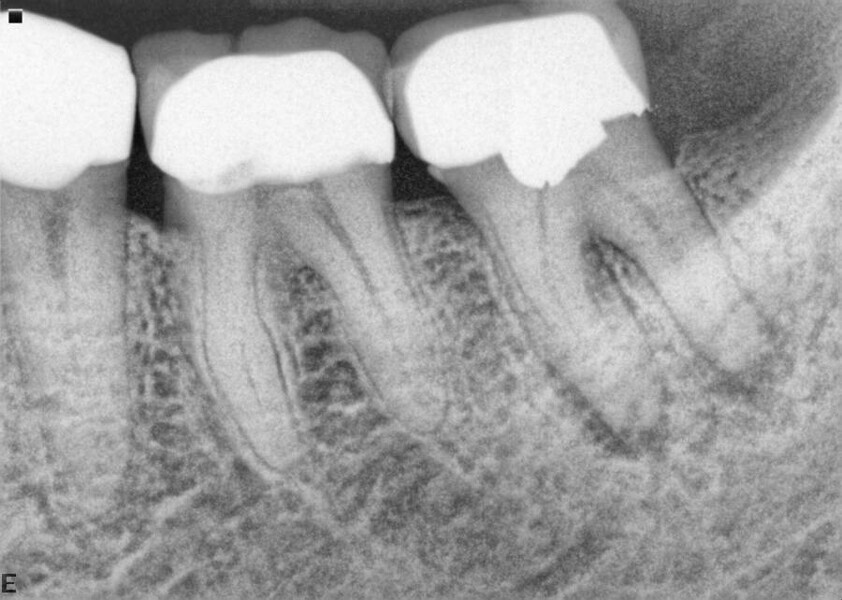

Fig. 17a: Case assisted with CBCT to determine anatomy pre-operatively. Note the multiple cross sections moving apically and the correlation to the 2-D view. Note also the conservative taper in relation to the root width. (Courtesy of Dr. Brett Gilbert)

Fig. 17b: Case assisted with CBCT to determine anatomy pre-operatively. Note the multiple cross sections moving apically and the correlation to the 2-D view. Note also the conservative taper in relation to the root width. (Courtesy of Dr. Brett Gilbert)